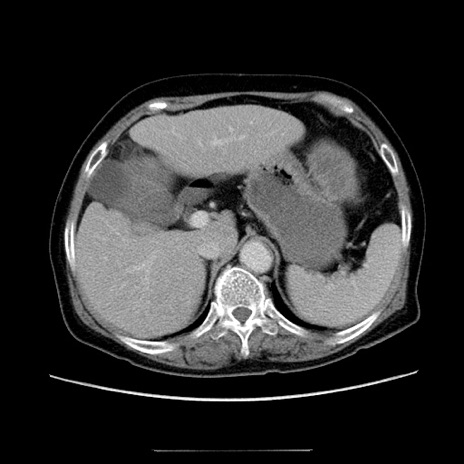

【症例】70歳代女性

【主訴】お腹が張る

【現病歴】1週間くらい前から腹部膨満の自覚あり。昨日夜から増悪したため、本日救急外来受診。

【身体所見】意識清明、BT 36.5℃、BP 165/106mmHg、HR 80bpm、SpO2 98%、腹部:膨満、軟、自発痛・圧痛なし、触診にて不快感あり、腸蠕動音:減弱

【データ】WBC 12600、CRP 1.04